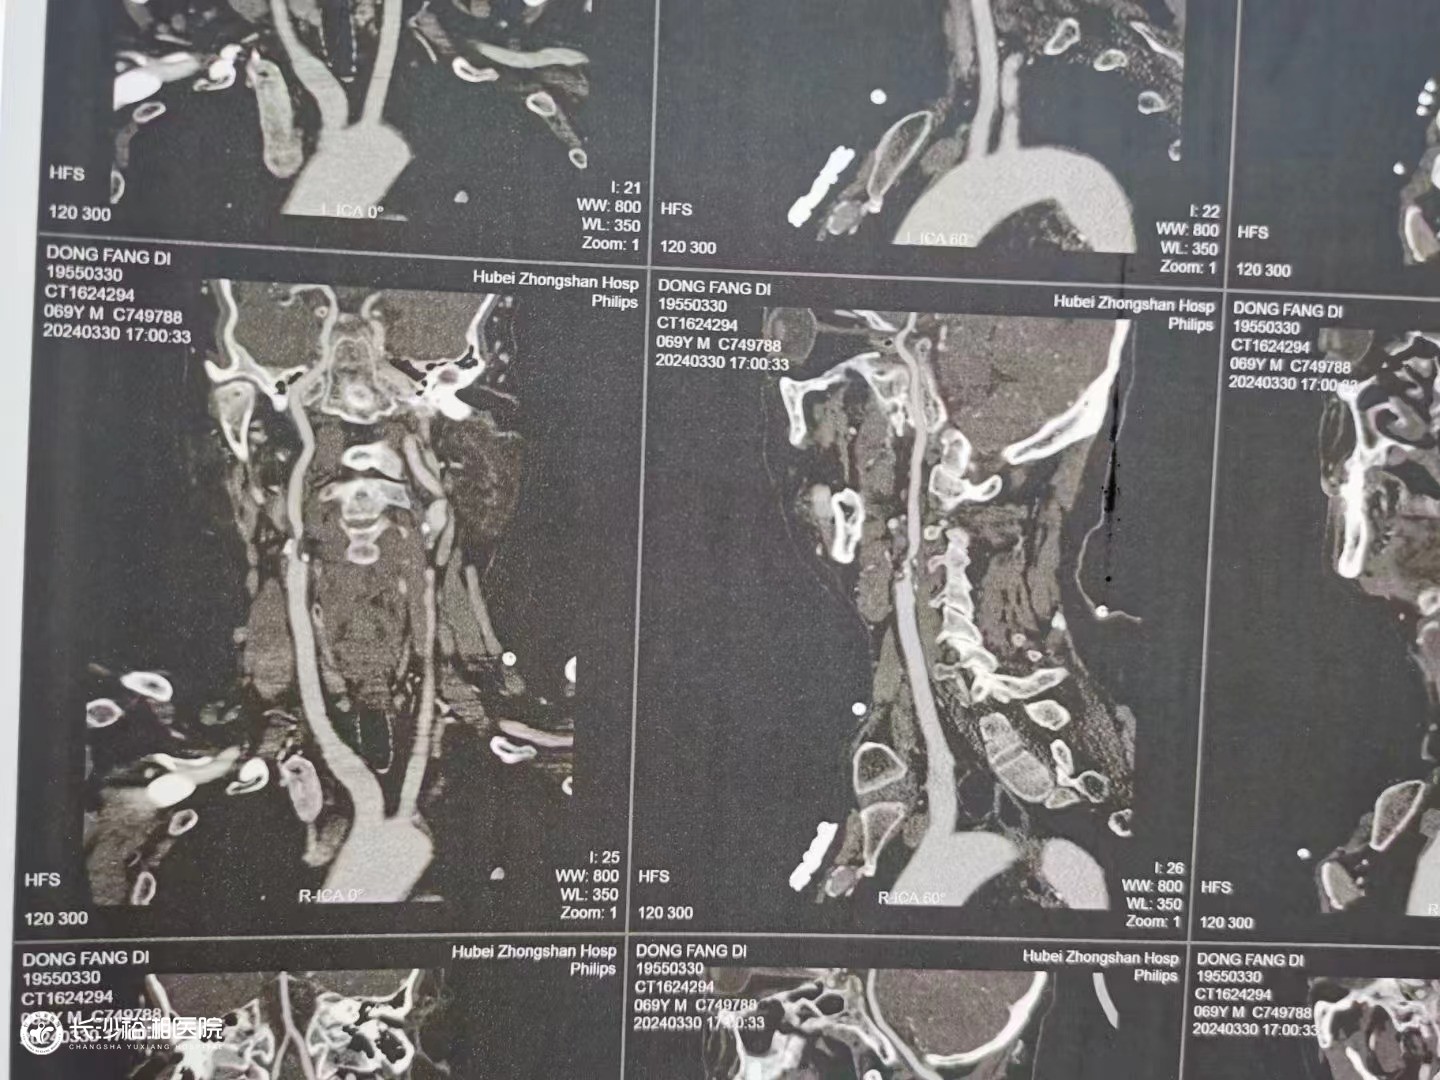

頸動(dòng)脈粥樣硬化斑塊切除術(shù)

腦卒中是我國(guó)城鄉(xiāng)居民死亡和殘疾的最主要原因,而頸動(dòng)脈狹窄是導(dǎo)致腦卒中的重要因素。頸動(dòng)脈狹窄的治療包括頸動(dòng)脈粥樣硬化斑塊切除術(shù)(CEA)、頸動(dòng)脈支架成形術(shù)(CAS)和藥物治療等。CEA被公認(rèn)是頸動(dòng)脈狹窄治療的金標(biāo)準(zhǔn),可以清除堵塞血管的增生斑塊,改善腦供血,顯著降低潰瘍型斑塊栓子脫落導(dǎo)致腦梗死的風(fēng)險(xiǎn),而且無(wú)植入物,手術(shù)費(fèi)用低,療效肯定。